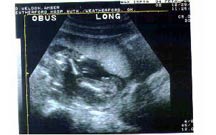

Jeremy and Amber's Son's Ultrasound

12/29/03